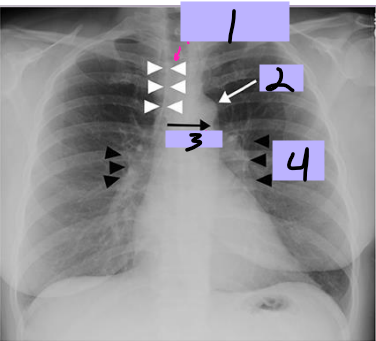

Aortic arch

#1

Superior vena cava

#2

Right pulmonary artery

#3

Right descending pulmonary artery

#4

Right atrium

#5

Right ventricle

#6

Left pulmonary artery

#7

Descending aorta

#8

Left ventricle

#9

Inferior vena cava

#10

Paratracheal stripe

#1

Aortic knob

#2

AP window

#3

Hila

#4